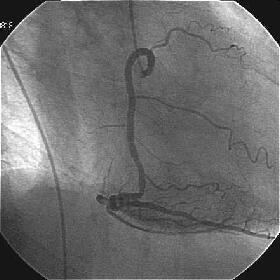

�ŏI�o���オ���IVUS�BIVUS��170507��septal���}����170509������2mm��O��

���̕����B

|

|

|

|

������������������������������������������������������������������������